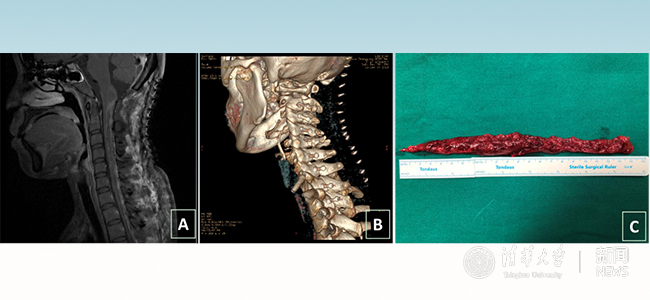

术后影像。图A示:肿瘤完整切除,图B示:椎板完整复位,图C示:肿瘤标本。